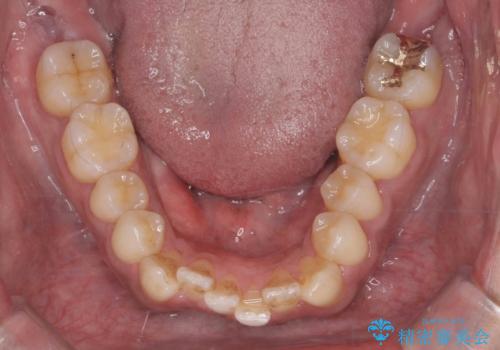

上はワイヤー部分矯正、下はインビザラインの部分矯正コースを行いました。

インビザラインだけでも治療は可能ではあると思いますが、ライトパッケージでは難しいと思います。

また、入れ替えを行う間左上の前歯だけで咬まなくてはならない状況になるため、マウスピース矯正単独で行うと時間がかかり、最悪神経が失活することもありますのでワイヤーがお勧めです。